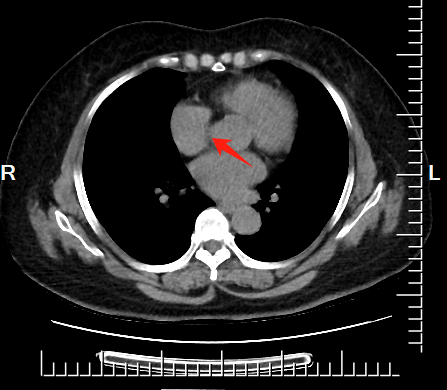

10、**男士,80岁

于2023年11月18日在银川仁泰体检部体检。低剂量肺部螺旋CT检查提示:右肺上叶肿瘤性病变(性质待定,右肺上叶尖段见约34*36mm紧贴胸膜不规则软组织实性密度影,可见分叶征、短毛刺征、胸膜凹陷征、空泡征(近边缘));后上纵膈气管后食管右侧胸椎右前可见39*17mm实性肿块影。双侧胸腔见少量积液。2023年11月20日电话通知客户到三甲医院进一步检查。2023年11月30日跟踪回访,客户已在当地三甲医院住院治疗。